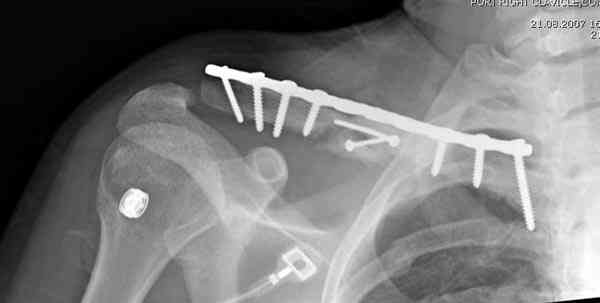

ГГШ> Результат стационарного лечения приведен на рентгенограмме (Xray_3).

Это картинка то есть через неделю после травмы, при выписке? Более чем приемлемо.

Я имею позицию стороннего наблюдателя в достаточно типичной ситуации: пациент -> лечение в одном учреждении -> выписка -> травмпункт -> направление в другое учреждение -> иной метод лечения (в данном случае - оперативное) -> жалоба родителей. Вот и причина :).

Дискуссия ведется вокруг вопроса о том, приемлемо или неприемлемо довольствоваться в результатами репозиции и стационарного лечения в первом учреждении (положительные ответы на эти вопросы отстаивают его сотрудники). Вот вам и повод :)). Сохраняя свою "стороннюю" позицию, позволю себе высказаться все же после паузы.

Распределение мнений по перечисленным выше категориям приведено на гистограмме (см. Рисунок 1). Мнения разделись, и в аудитории преобладает убеждение, что сохранение смещения ключи.цы на величину диаметра без кортикального контакта между отломками и смещением до 3 см по длине у подростка 15 лет допустимо.

Оценка положения костных фрагментов должна осуществляться по рентгенограммам, вы.полненным в двух проекциях. Стандартная ( и почему.то считающейся достаточной в большинстве наших лечебных учреждений) передне.задняя проекция дополняется шейной проекций под уг.лом 45°. Смещения: расхождение в поперечном направлении, отсутствие кортикального контакта, укорочение ключицы более 1,5 см . недопустимы и должны быть устранены (11,12).

Рисунок 1 Распределение мнений травматологов по вопросу о допустимости сохранения смещения ключицы на величину диаметра без кортикального контакта между отломками и смещением до 3 см по длине (См. определение категорий в тексте)

Уважаемая Г.В. Полностью согласен с Вашим постом.Закрытая репозиция и кольца Дельбе отлично зарекомендовали себя за 35 лет практики. В обсуждаемом случае представленные Р-граммы сами говорят за себя, 1 снимок (до лечения) и 3 снимок (после лечения) абсолютно идентичны, 2 снимок сделан в несколько иной позиции.Как говорится "комментарии излишни". Согласитесь, что результат лечения мог бы быть и лучшим.